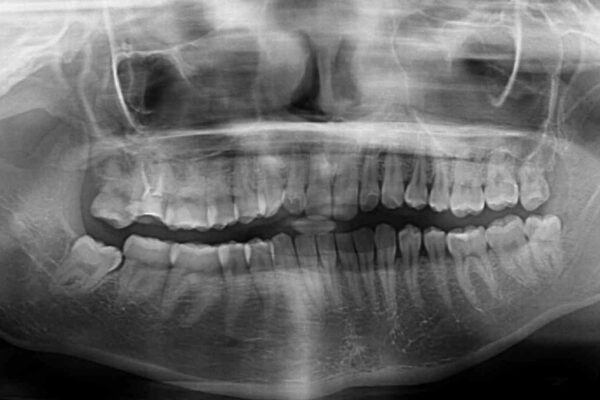

根管治療を行ったままの奥歯と、矯正治療の後戻りを気にして来院された患者様です。

治療計画

根管治療された歯に症状はなく、オールセラミッククラウンにて補綴治療を行うこととしました。

矯正治療の後戻りは軽微であったため、インビザラインの簡易パッケージであるインビザライン・ライトを用いて歯列を整えることとしました。

治療後について

クラウンはよりよい咬み合わせで装着したいため、インビザラインを1セット使用して概ね歯列を整えた時点で補綴治療を行い、その後仕上げの矯正治療を行いました。